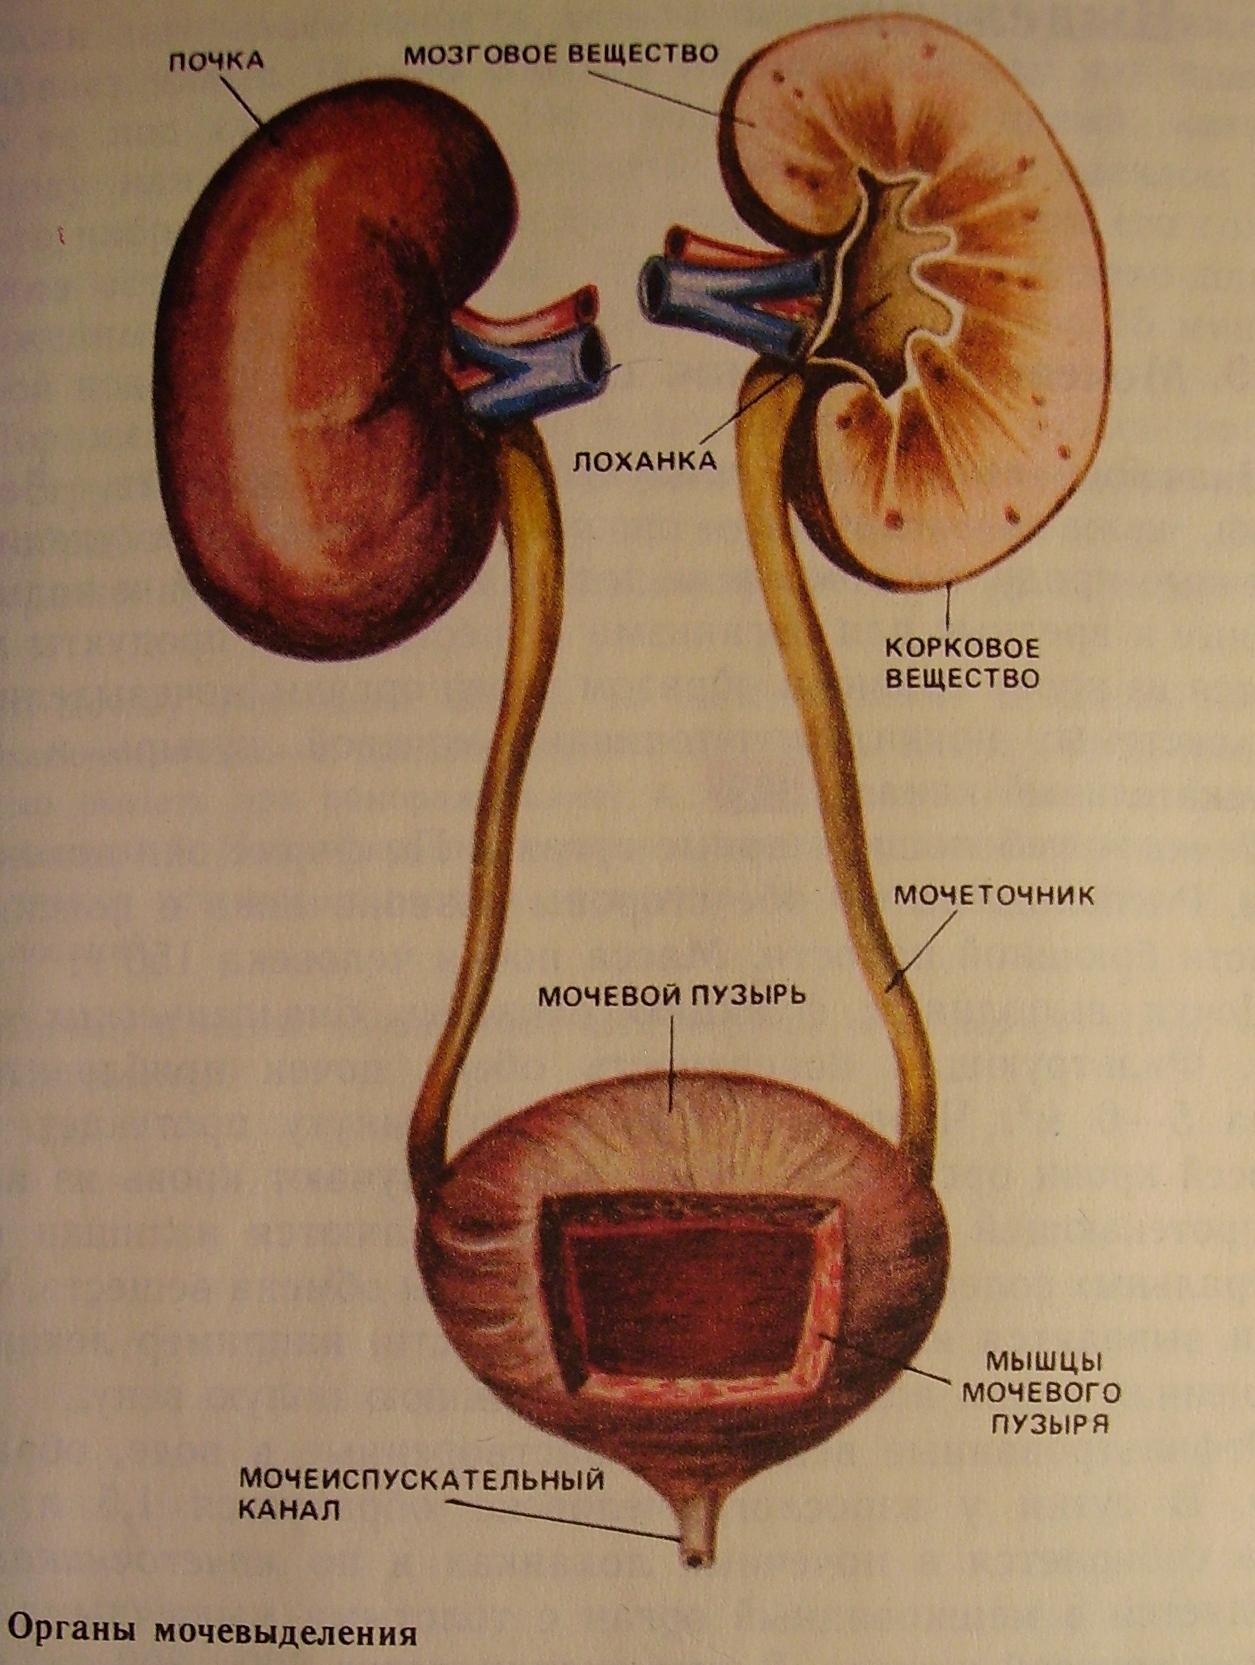

Интраренальная лоханка: рентгеновские снимки и примеры